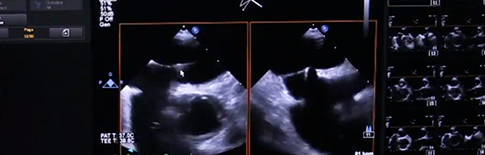

Το μεσημέρι της Παρασκευής, μεταδόθηκαν ζωντανά έξι επεμβατικές πράξεις, με τη χρήση καινοτόμων μεθόδων και ιατρικού εξοπλισμού, τις οποίες συντόνιζε ο καθηγητής Κώστας Τούτουζας. Το Iatronet βρέθηκε στο αμφιθέατρο του "Ιπποκρατείου" και τις μεταφέρει:

Η πρώτη, αφορούσε έναν 81χρονο άνδρα με χρόνια αποφρακτική πνευμονοπάθεια, ο οποίος είχε υποβληθεί το 2001 σε αντικατάσταση μιτροειδούς βαλβίδας, ενώ είναι υπερτασικός και νεφροπαθής.

Ο ασθενής διαγνώστηκε με σοβαρή στένωση αορτικής βαλβίδας και υποβλήθηκε σε μη χειρουργική αντικατάστασή της. Δεν οδηγήθηκε στο χειρουργείο, καθώς αντιμετώπιζε τον κίνδυνο να υποστεί εμβολικό επεισόδιο.